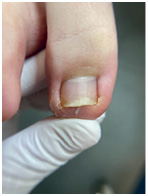

![]() ![]() ![]() Откат в динамике восстановления ногтя после протезирования Вросший ноготь

Самая распространенная и самая сложная работа, с которой мы сталкиваемся. Вросший ноготь причиняет боль, поэтому люди часто боятся обращаться за помощью – представляют себе страшную операцию с длительной реабилитацией. ![]() ![]() ![]() ![]() Работа с вросшим ногтем Одну нашу клиентку внезапная боль настигла в поездке. Она тут же решила обратиться к специалисту, но что-то пошло не так. В ближайшей студии подологии ей срезали вросший сегмент и благополучно забыли его достать. Проблема не исчезла, и девушка вновь обратилась к подологу, только уже в нашу студию. Наш специалист промыл рану, проложил тампонаду и установил титановую нить. Из-за образования грануляции рана кровила, поэтому система слетела через 3 дня. Именно для таких случаев у нас действует гарантия на коррекционные системы – в течение двух недель после установки при необходимости мы поменяем систему бесплатно. На втором приеме специалисту все-таки удалось достать вросший сегмент, который причинял столько неудобств. Сейчас девушка ходит с системой чуть послабее, и мы ждем ее на плановый прием для коррекции системы и наблюдения динамики. Хорошо, что наша героиня не стала терпеть боль и быстро обратилась за помощью повторно. Чем раньше вы направитесь к специалисту, тем больше шансов быстро и безболезненно избавиться от проблемы. Причины врастания 1. Гипергидроз стоп (повышенная потливость). 2. Неправильная обработка ногтей: когда вы обрезаете их слишком глубоко или срезаете уголки. 3. Неправильно подобранная обувь, особенно слишком узкая в переднем отделе стопы. 4. Ортопедические проблемы, например плоскостопие. 5. Травма ногтя: ноготь после травмы отрастает, дистальный валик закрывается, и стенки ногтя начинают врастать. Как идентифицировать вросший ноготь Чаще всего проблема встречается на больших пальцах ног. Тревожные сигналы: • кожа вокруг ногтя краснеет, затем на ней появляется отечность, становится больно дотрагиваться до ногтя; • из поврежденных областей начинают сочиться кровь и гной; • вросшая часть ногтя становится плотнее, болезненность переходит в хроническую форму. Топ-3 совета как избавиться от вросшего ногтя без операции Как лечить Есть два варианта – радикальный и консервативный. Радикально решают проблему хирурги – просто удаляют проблемный ноготь. К сожалению, этот метод не решает проблему полностью, очень часто она рецидивирует. Радикально решить проблему без рецидива можно, только если удалить ноготь вместе с матриксом. Но тогда ноготь уже не будет таким же красивым и ровным, как до операции. Подологи – консерваторы. Специалист аккуратно отрезает кусочек ногтя, который вызывает воспаление. Это больно? Все индивидуально: кто-то совсем не испытывает дискомфорта, кому-то приходится немного потерпеть. Но сильной боли нет – обычно страх сильнее, чем боль:) Даже дети вполне спокойно переносят процедуру. Мы работаем без анестезии, но она и не нужна, потому что в работе мы не затрагиваем ранку. Сразу после процедуры становится значительно легче, а для полного заживления требуется от недели до месяца. Вросший ноготь. Простой способ вылечить вросший ноготь без боли ![]() ![]() ![]() ![]() |